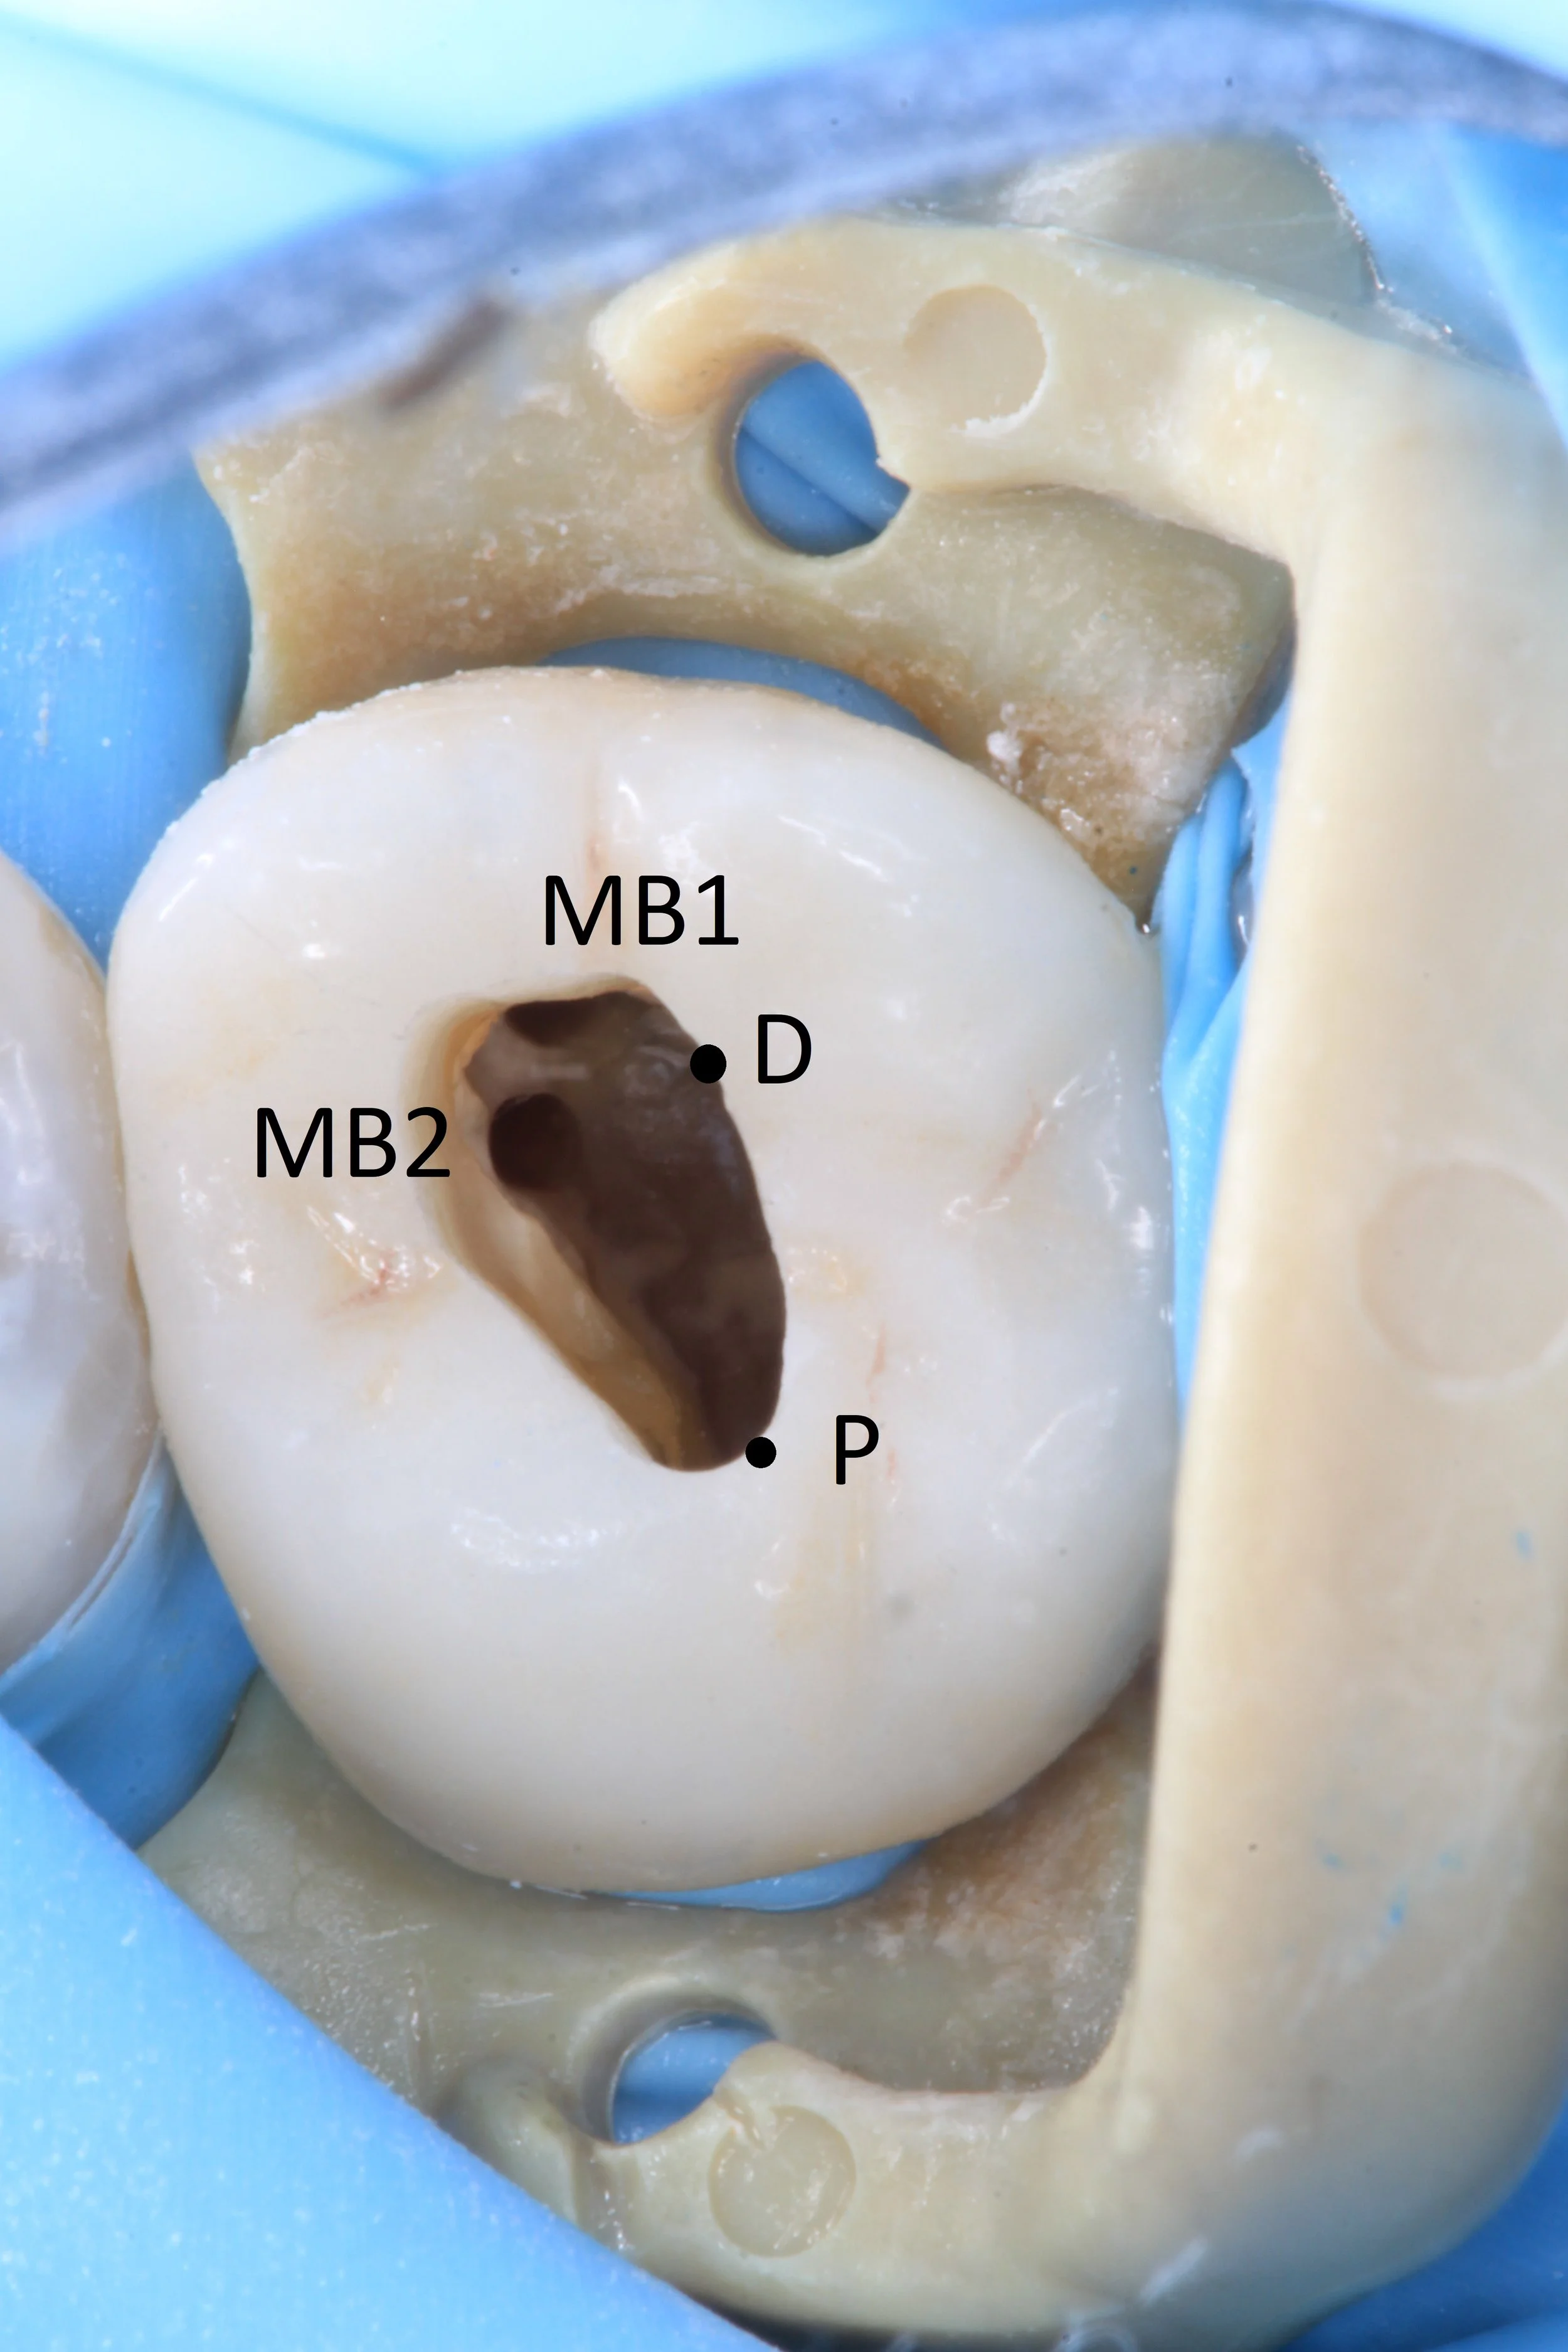

Position of MB2 orifice in the more traditional position. About 3-4mm palatal to MB2 orifice.